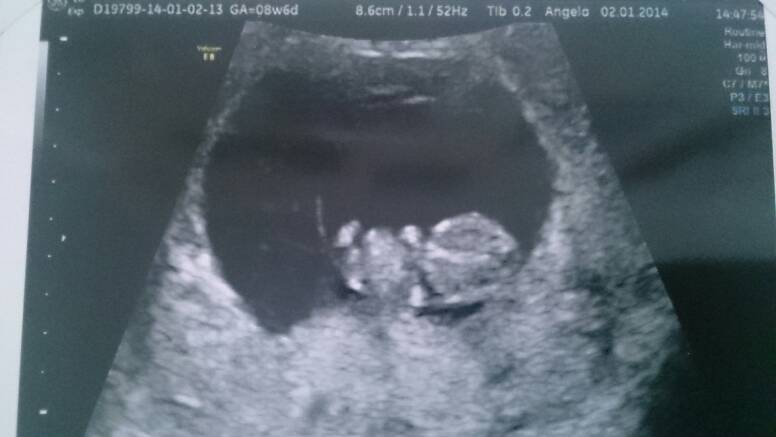

Sorki bo zdjęcie se zdjęcia..

Przez brzuch wszystkie, pierwsze 8t3 drugie dwa 8t6d.

Kochana nie wiem właśnie.. Joasia chyba pisała, że miała w równym 8tc i widziała? Potwierdź proszę. U mnie napewno 3 dni po 8 było widać pieknie.

Lilith o kurcze super widac dzidzie! Dzieki za zdjecia, to moze ja teraz tez bede sie upierac przy usg brzusznym? Sama nie wiem....W sumie to mam troche metlik w glowie, czesc osob mowi ze usg zadne nie ma wplywu na malucha, czesc mowi ze kazde usg ma wplyw a to dowcipne to juz w ogole inwazyjne grzebanie i lepiej tego nie robic.... Wkurza mnie to,mze kazdy mowi co innego, a ze jestem po stracie to jestem podatna na te wszystkie dobre rady:/:(

Lilith A zdjęcia bomba! Pierwszy raz takie widzę i nie mogę się napatrzec :D